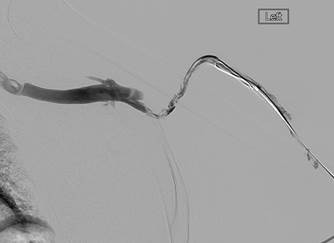

Injerto AV con trombosis y con estenosis en anastomosis venosas.

Catéteres DVX de AngioJet en injerto AV.

Imagen tras la activación del sistema AngioJet en el lado venoso del injerto AV.

Imagen tras la activación del sistema AngioJet en el lado arterial del injerto AV.